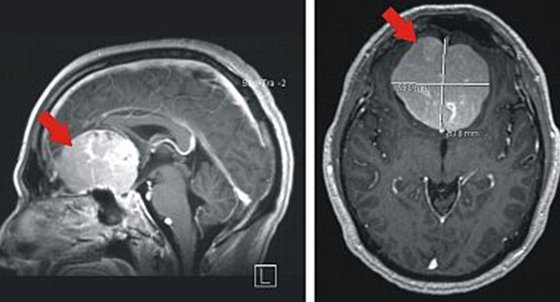

Vorstellung Aus Rheinland Pfalz Meningeom Parietal